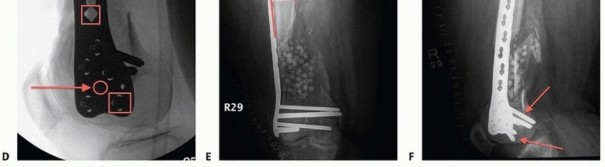

### FIG 11 • Morbidly obese female with a severely comminuted and open right distal C3 femur fracture. A,B. AP and lateral radiographs showing the amount of comminution, bone loss, and distal nature of the injury after the initial irrigation, débridement, and bridging external fixation. C,D. Intraoperative fluoroscopic images during application of a variable-angle locking plate. The AP shows the “central screw” to aid in reestablishment of the anatomic axis of the femur (parallel lines solid , screw; dashed , joint line). The lateral view shows the central screw, which is a fixed-angle hole (arrow and circle), as opposed to the variable-angle holes (red box ; both for the combination holes and isolated variable-angle screws). E,F. Two-week postoperative radiographs. The AP view shows the proximal screws placed perpendicular (dashed arrows) to the plate even through the variable-angle portion of the combination holes, which was facilitated by the targeting device. Both views demonstrate the advantage of the variable-angle locking holes distally to allow for additional fixation in this short distal segment with a more posterior and distal trajectory (solid arrows on lateral view). The bone substitute placed for the bone defect (white pellets) are also clearly visualized. (continued) 475

---

### FIG 11 • (continued) G,H. Five-month follow-up films showing replacement of the calcium sulfate beads with successful consolidation of the metaphyseal comminution. The flexibility of fixation constructs can be increased by the use of a technique referred to as far cortical locking. Specialized screws are used, in which the screw locks into the plate and only engages the far cortex. This has been thought to improve fracture healing. 5 The “polyaxial” locking plates have been shown to be biomechanically sound in the management of supracondylar femur fractures. 12, 18 ## Preoperative Planning Surgical timing can be affected by the following: Soft tissue issues Medical condition of the patient Adequacy of available operative team Availability of implants The approach must take the following issues into consideration: The ability to incorporate lacerations in open fractures into the incision ( FIG 13) can be useful and should be considered. However, this is not always necessary or possible.

--- TECH FIG 6 • A,B. Patient seen in FIG 15C,D, with the guidewire now pulled back and an appropriately sized screw placed. Once the AP position is obtained, the plate is stabilized proximally. The plate should be temporarily stabilized to the bone proximally. Before the temporary stabilization, the length and rotation must be checked. Ideally, if the temporary fixator is in place, these two parameters have been maintained during the course of the operation. If no screw targeting guide is present, a percutaneous provisional fixation pin can be used to stabilize the plate. If a targeting guide is used, then a soft tissue guide for the most proximal hole is placed percutaneously and a drill bit or guidewire is used to stabilize the plate. The variable-angle locking plates also have proximal shaft targeting devices; however, variable locking trajectories can only be accomplished outside the targeting device and can be cumbersome. Generally, variable-angle locking is not necessary in the shaft and locking screws collinear with the hole can be placed through the targeting device. ( FIG 11E, red arrows showing perpendicular nature of locking screws; FIG 11F, variable-angle locking screws in the shaft are useful in cases where there is a preexisting hip replacement with a femoral component.) Again, the flexion-extension reduction should be checked. This procedure creates our “box” construct, which aids in the placement of screws through the targeting device (if used) and in temporary stabilization of the fracture construct. ### Screw Placement If the intercondylar split is going to be stabilized by screws through the plate, partially threaded screws or overdrilled fully threaded screws should be used first to provide interfragmentary compression. Specially designed conical screws for certain systems exist, or large partially threaded screws can be used ( >4.5 mm). This also compresses the plate to the bone. Once the articular injury is addressed, at least two additional locking screws should be placed into the distal segment to secure the plate and the alignment. The trajectory of distal locking screws can be assessed on the notch view to ensure that penetration through the intercondylar notch does not occur ( TECH FIG 6; see FIG 15C for C-arm setup and position for this image). Before placing the locking screws, the length, rotation, and alignment must be checked again if no fixator or distractor is in place holding the fracture alignment. The plate can be locked to the distal segment and then used to manipulate the distal segment relative to the shaft for the flexion-extension reduction. This, however, is predicated on proper distal alignment of the plate. Otherwise, once the plate is fixed to the distal segment in a malposition and the fracture reduced, the plate may be anterior or posterior on the shaft. The distal screws in a variable-angle locking plate are noncircular to allow for the variable-angle locking mechanism. Screws can be placed directly collinear or with a “variability” of 15 degrees in any direction depending on the system used (see FIG 11D, square outline). ### Attaching the Distal Segment to the Shaft The distal segment is now fixed and can be attached to the shaft. If there is malalignment in the coronal plane but the sagittal plane alignment is reduced, the shaft can be “pulled” to the plate by means of various threaded devices or a nonlocking screw that can be placed freehand under fluoroscopic guidance or through a targeting jig ( TECH FIG 7). ### Placement of Additional Screws Once proper reduction of the fracture is temporarily achieved and the plate is in proper position, additional screws can be placed. If the targeting screw guide is used, percutaneous locking screws can be placed through the soft tissue drill or screw guides ( TECH FIG 8A-C). If no targeting guide is available, fluoroscopic guidance and a percutaneous method can be used freehand. 484